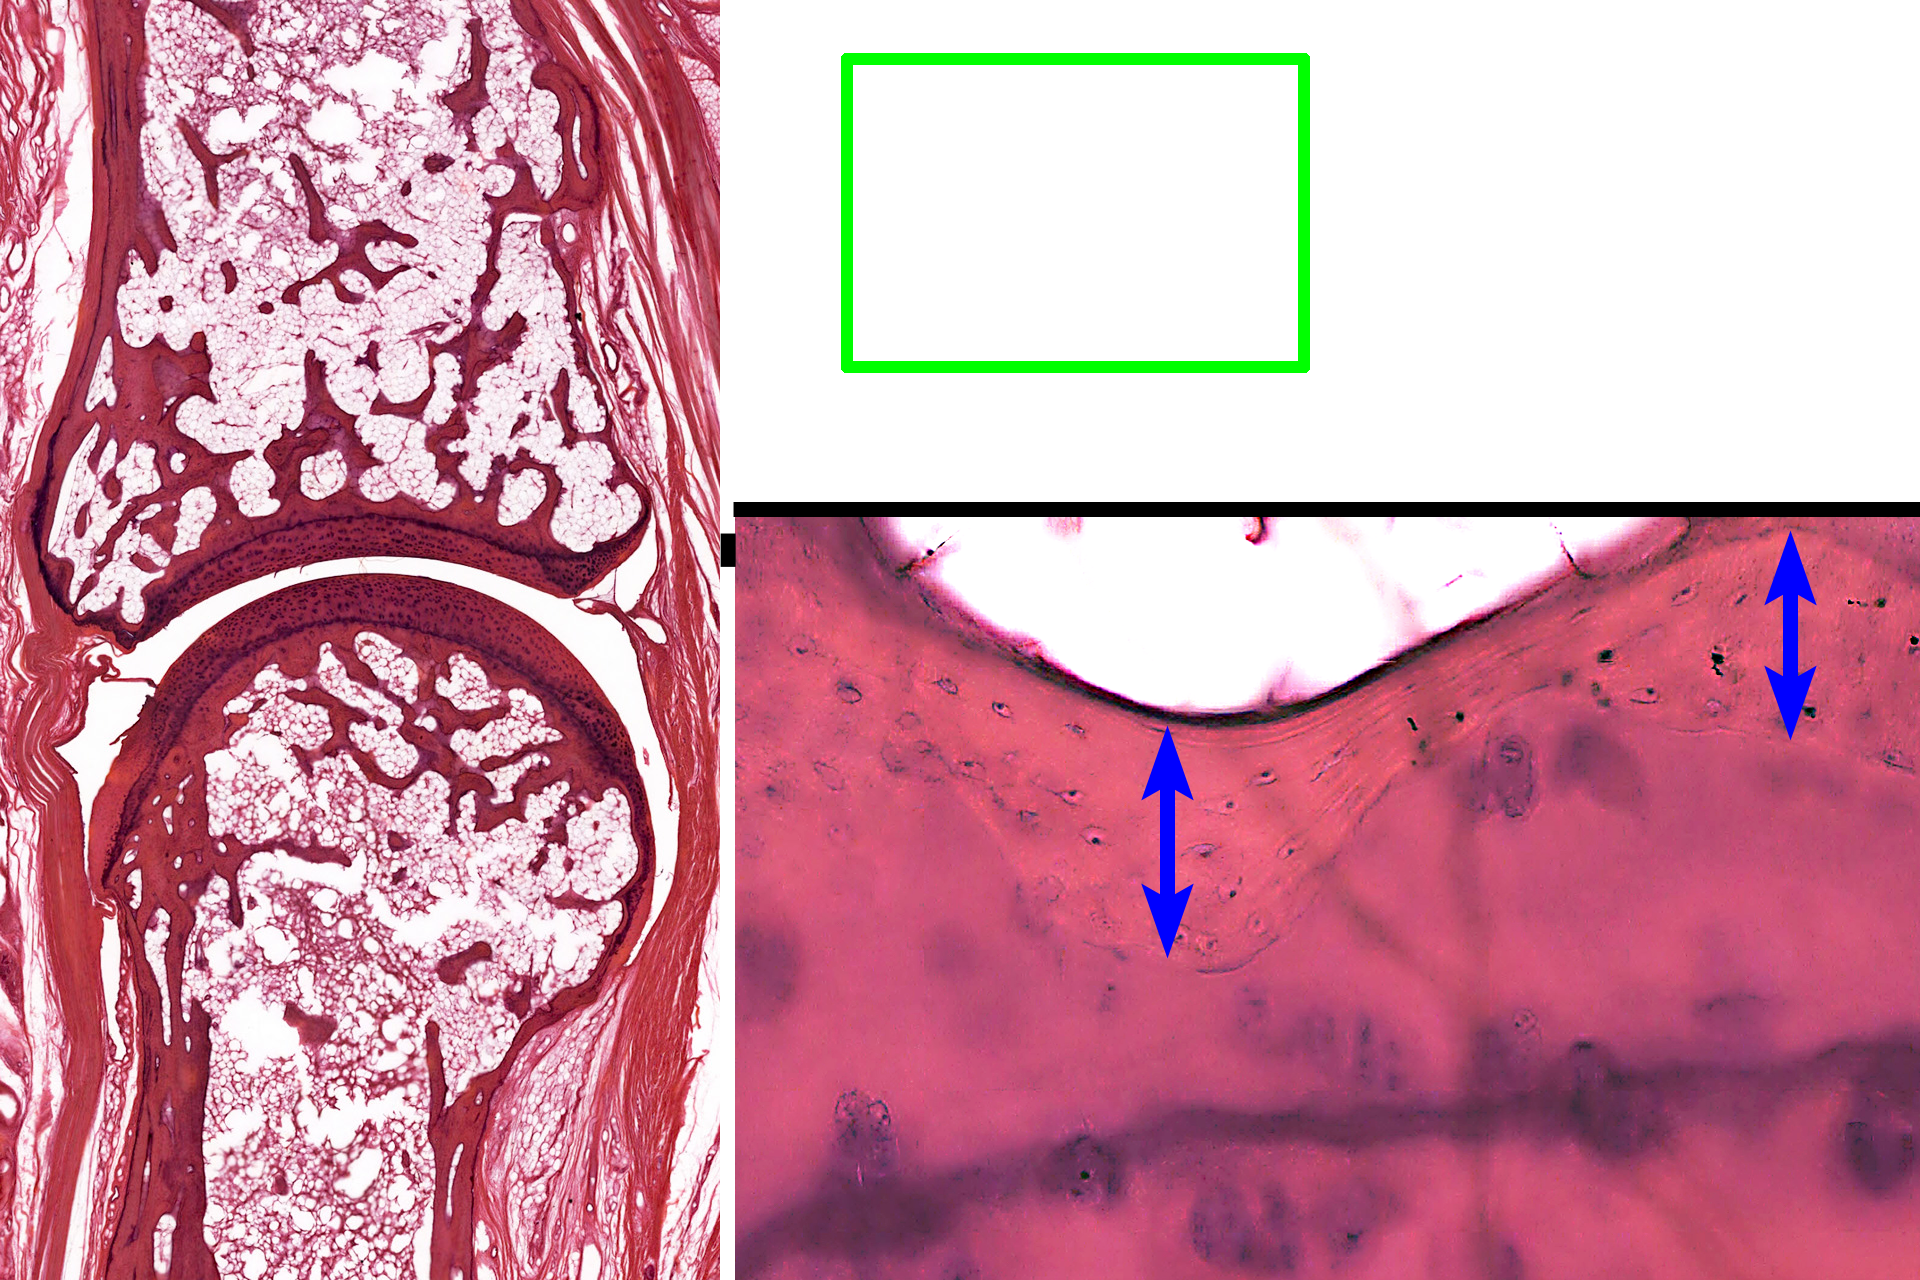

This higher magnification of the area indicated by the green rectangle shows the interface of the compact bone of the epiphysis with articular cartilage. Osteocytes in lacuna are evident in the compact bone.